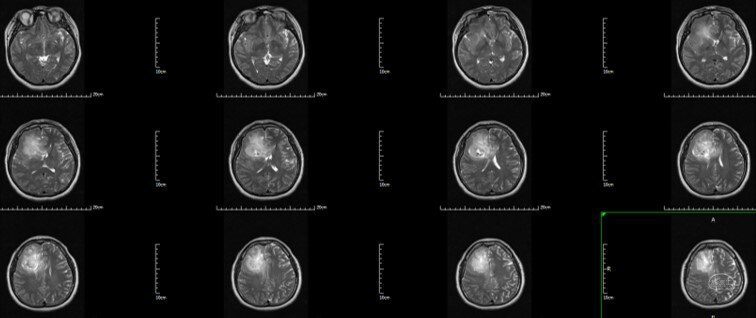

术前T2 Flair:右额-胼胝体-岛叶胶质瘤

术前T2